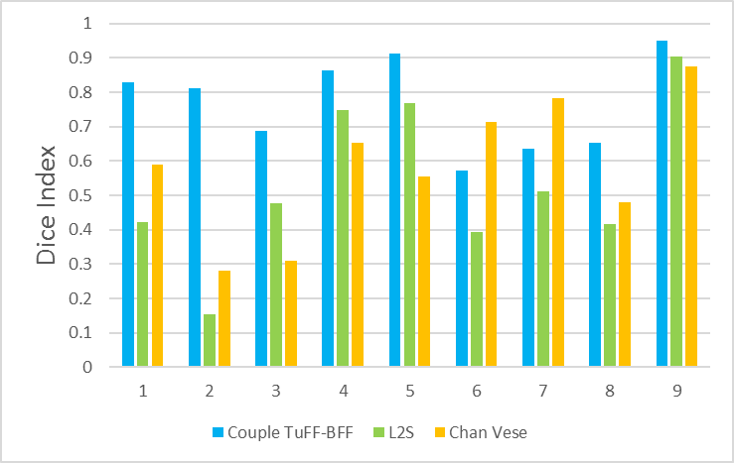

In our experiments, we compare the coupled TuFF-BFF microglia segmentation results with those given by L2S [21] and the Chan-Vese segmentation method [22]. The groundtruth in 3D was attained by manually tracing the object slice by slice from the z-stack. It must be noted that this was done by eye and could have some error. Figure 2 shows the visual comparison of the segmentation results for our dataset. Our result shown on the third column captures both the soma and processes. Figure 3 shows the Dice coefficient comparison of each segmentation method to the ground truth. Since the soma is much larger than the fine processes in the microglia, the processes have less volumetric impact on the similarity score. As explained in Section 1, segmenting the processes is important for quantifying the extension from the soma and its volume of surveillance. We use the Dice coefficient to quantitatively compare the ramification by taking the convex hull of the resulting segmentation. The Dice coefficient is a similarity measure that is computed using with where is the ground truth and is the compared image.

From Figure 4, the average Dice score for coupled TuFF-BFF was 0.77, compared to 0.53 for L2S [21] and .58 for Chan-Vese [22]. It must be noted that L2S required manual user initialization for each 2D image in the stack. While the Chan-Vese method has automatic seed selection, our coupled TuFF/BFF method was the only method that was a true 3D segmentation algorithm. L2S could not consistently capture the entire processes due to the intensity inhomogeneity throughout the object and background noise. The Chan-Vese segmentation could capture the extensions of the processes but did not work well with noise and attained false positives in the reconstruction. Since our method uses the tubular and blob information of the object to separate foreground and background, the segmentation only evolved within the object boundaries.